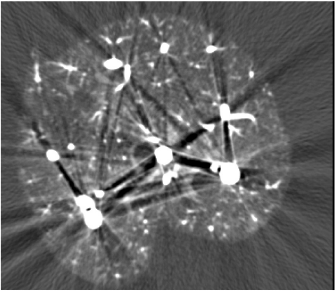

此外,当身体中存在与水原子序数相差很大的物质,如造影剂等,水束硬化矫正也会失效。这些高密度物质的衰减特性与水相差很大,使得水束矫正无法发挥作用,如下图2. 所示,仅对图1. 左,做水束硬化矫正,虽然软组织不均匀情况得到缓解,但仍存在骨硬化伪影。

Fig 2. 对 Fig 1. 左做水束硬化矫正结果,并不能矫正骨硬化